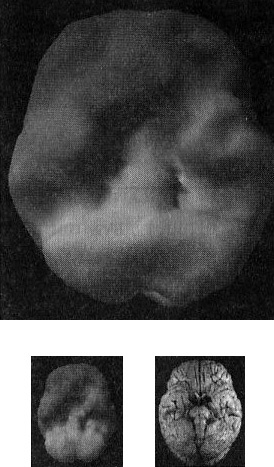

От этой болезни страдала мать моей подруги Айзы Гиббонс, основавшей ряд центров поддержки для людей с БА и членов их семей. Мать Лизы из доброй, мягкой женщины превратилась в озлобленного, иррационального и агрессивного человека (рис. 2.8).

Мозг пациента с болезнью Альцгеймера

Рис. 2.8 Вид сверху

Значительно снижена активность в задних частях мозга